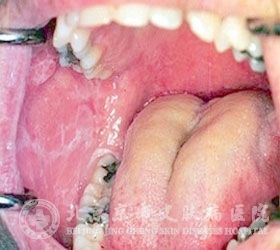

口腔扁平苔藓的特点是什么?口腔扁平苔藓严重困扰着我们身边的很多人,因此有很多患者关心这个口腔扁平苔藓问题,但目前有很多患者对口腔扁平苔藓了解不足,错过了较佳治疗口腔扁平苔藓时机,从而导致口腔扁平苔藓病情发展严重,增加了口腔扁平苔藓患者痛苦,同时也增加了口腔扁平苔藓的治疗难度。知道口腔扁平苔藓有什么特点,就可以及早的发现口腔扁平苔藓,采取措施,治疗口腔扁平苔藓。

北京京城皮肤医院指出,口腔扁平苔藓一般是在急性期长期没有及时恰当处理、拖延时间较久的情况下发生。口腔扁平苔藓皮损以针尖大小丘疹、并伴发白色的粘膜破损,特别是遇到冷热食物或者刺激性食物时,会出现疼痛感。